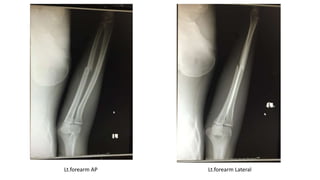

Lt.forearm AP Lt.forearm Lateral

Diagnosis: Closed fracture left shaft of ulna